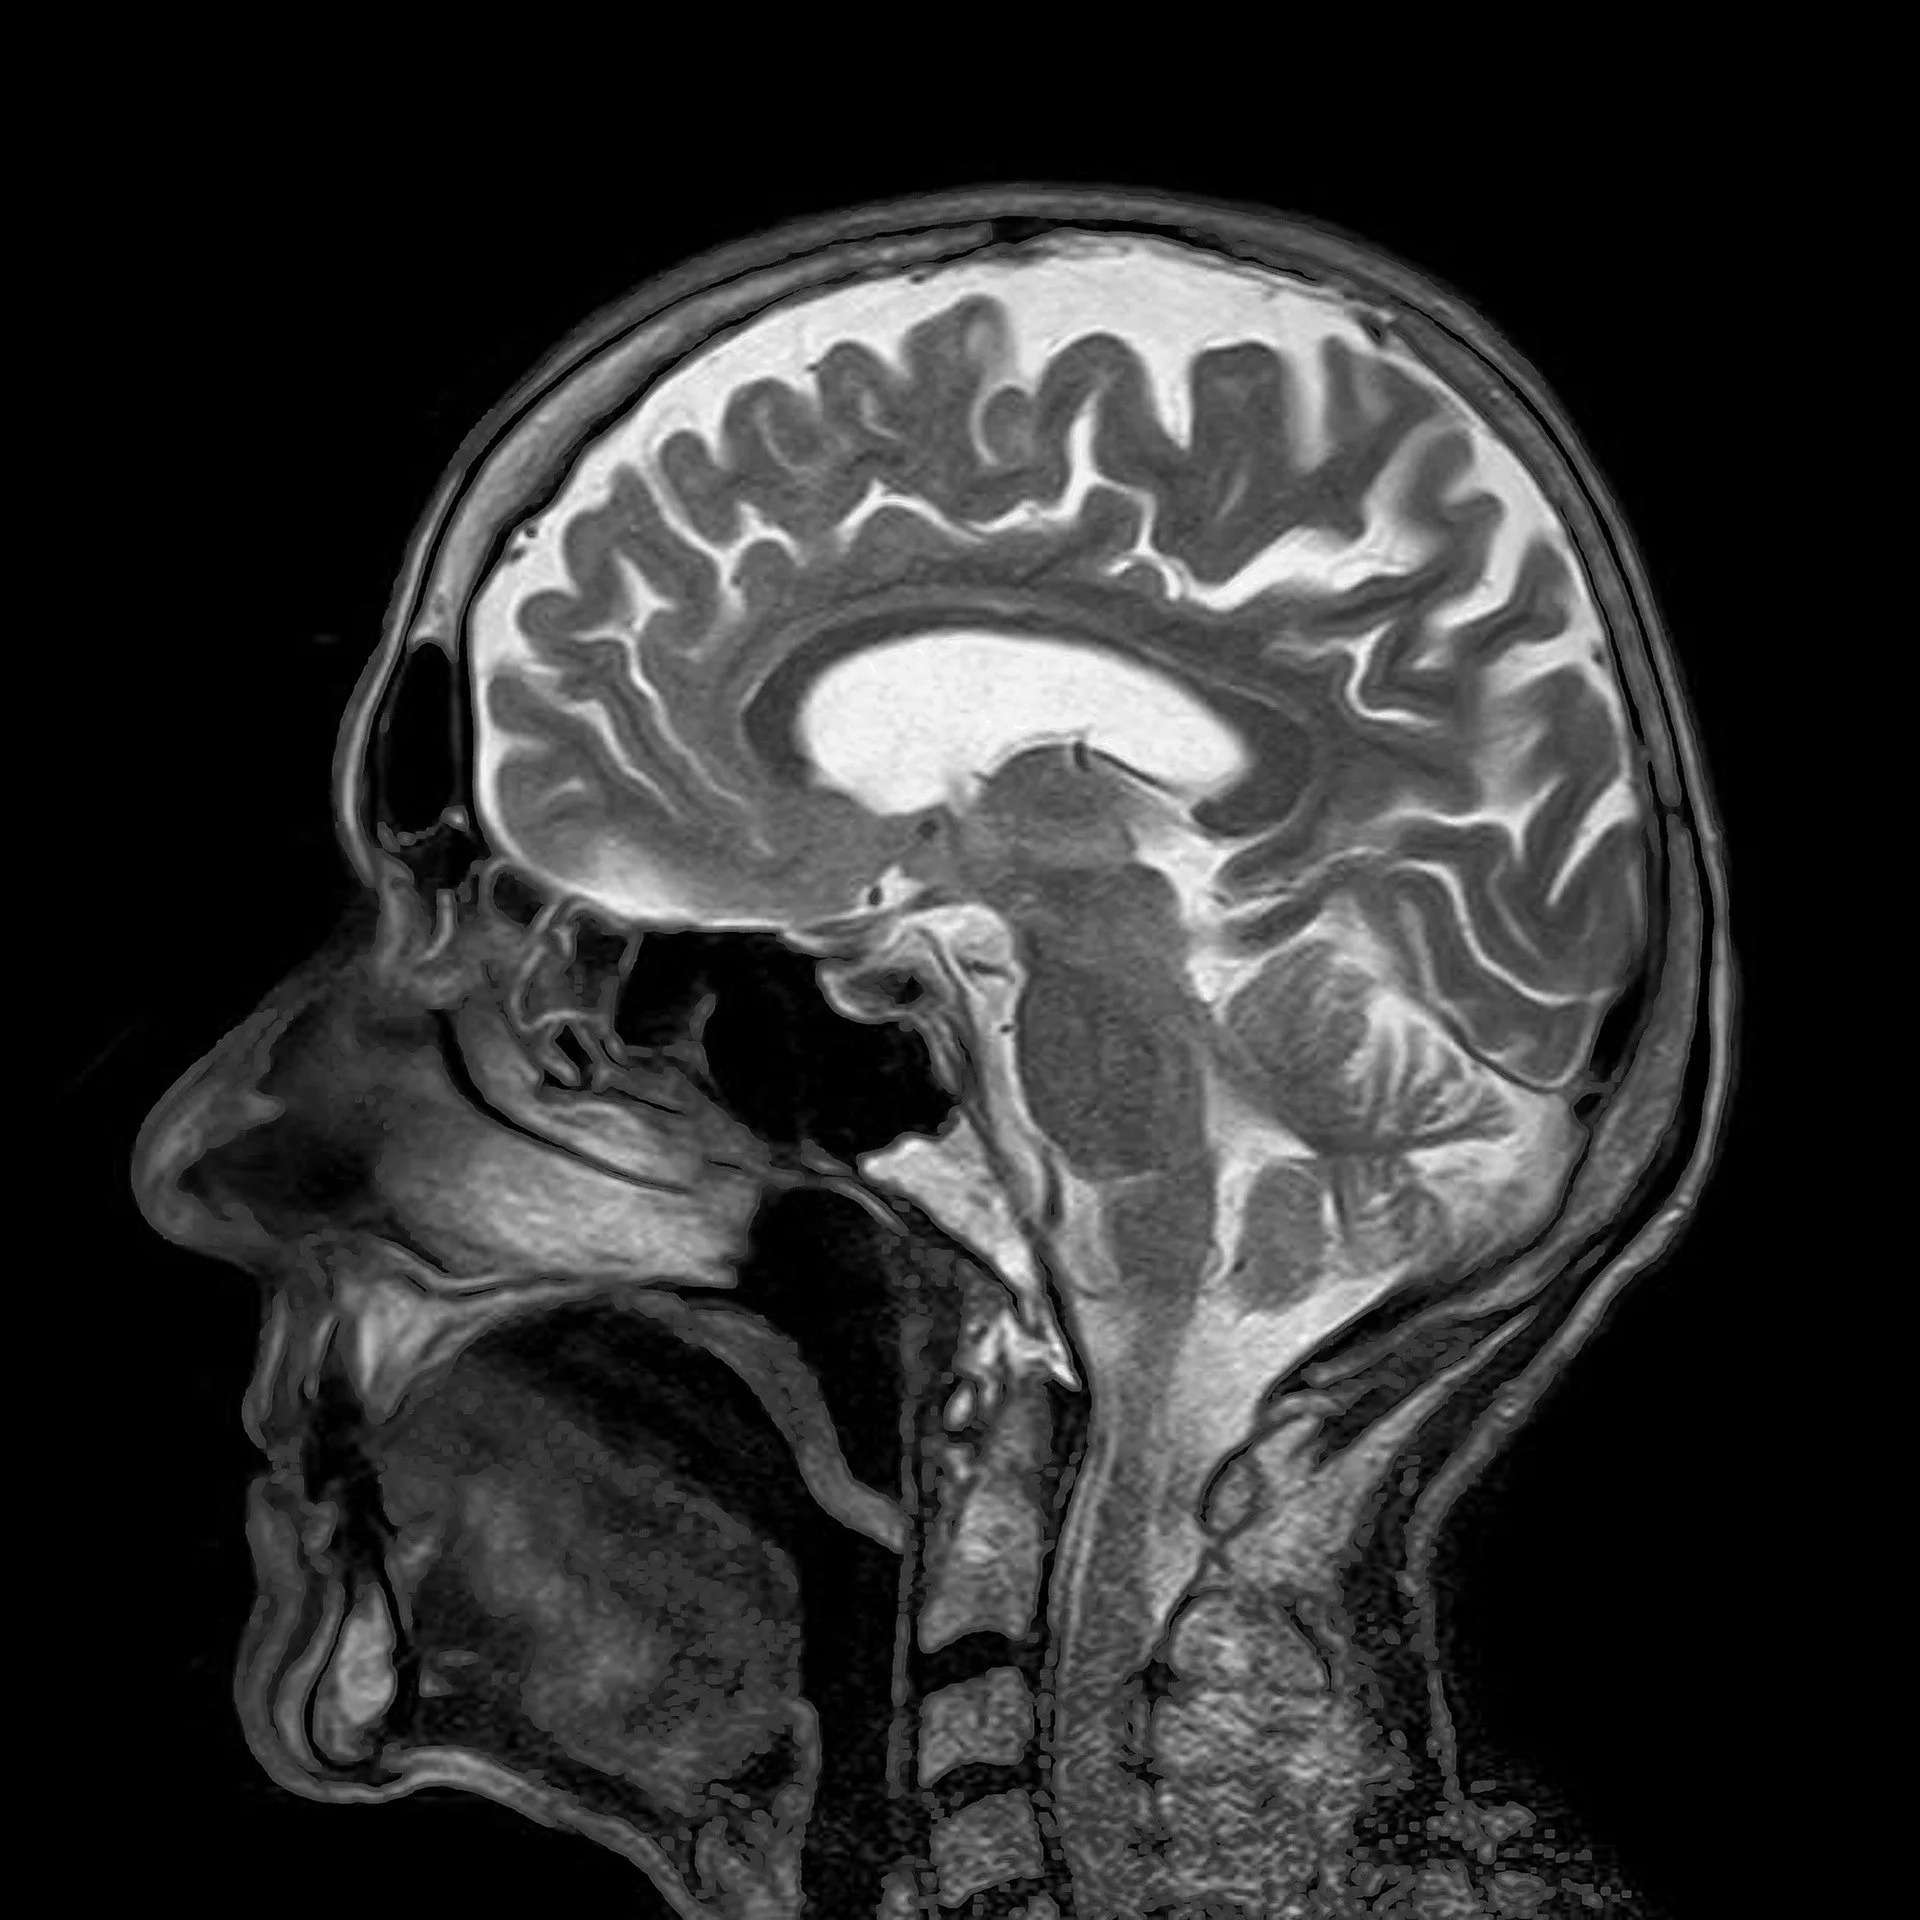

Magnetic Resonance Imaging (MRI) is a revolutionary medical imaging technique that uses a strong magnetic field and radio waves to generate detailed images of the body's internal structures. It provides valuable information for diagnosing and monitoring a wide range of medical conditions without using ionising radiation.

During an MRI scan, the patient lies on a bed that slides into an open cylindrical bore called an MRI scanner. The scanner has a magnetic field and uses radio waves, causing the atoms in the body's tissues to emit signals. Specialised detectors in the scanner capture these signals, which are then processed by a computer to create detailed cross-sectional images of the body.

• MRI provides highly detailed images of the body's internal structures, including organs, soft tissues, bones, and blood vessels. It allows healthcare professionals to visualise and evaluate abnormalities, diseases, injuries, and other conditions more precisely.

• MRI can also provide functional information about the body's tissues and organs, such as blood flow, metabolism, and brain activity. Functional MRI (fMRI) is a specialised technique used to study brain function.